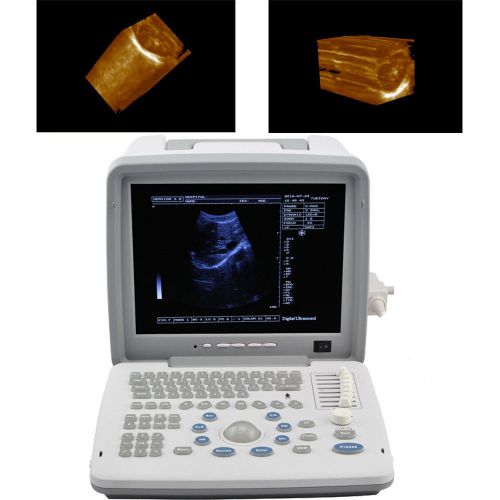

3D Portable Notebook Digital Laptop Ultrasound machine Scanner CONVEX PROBE

3D Full Digital Portable Ultrasound Scanner convex & Transvaginal 3D workstation